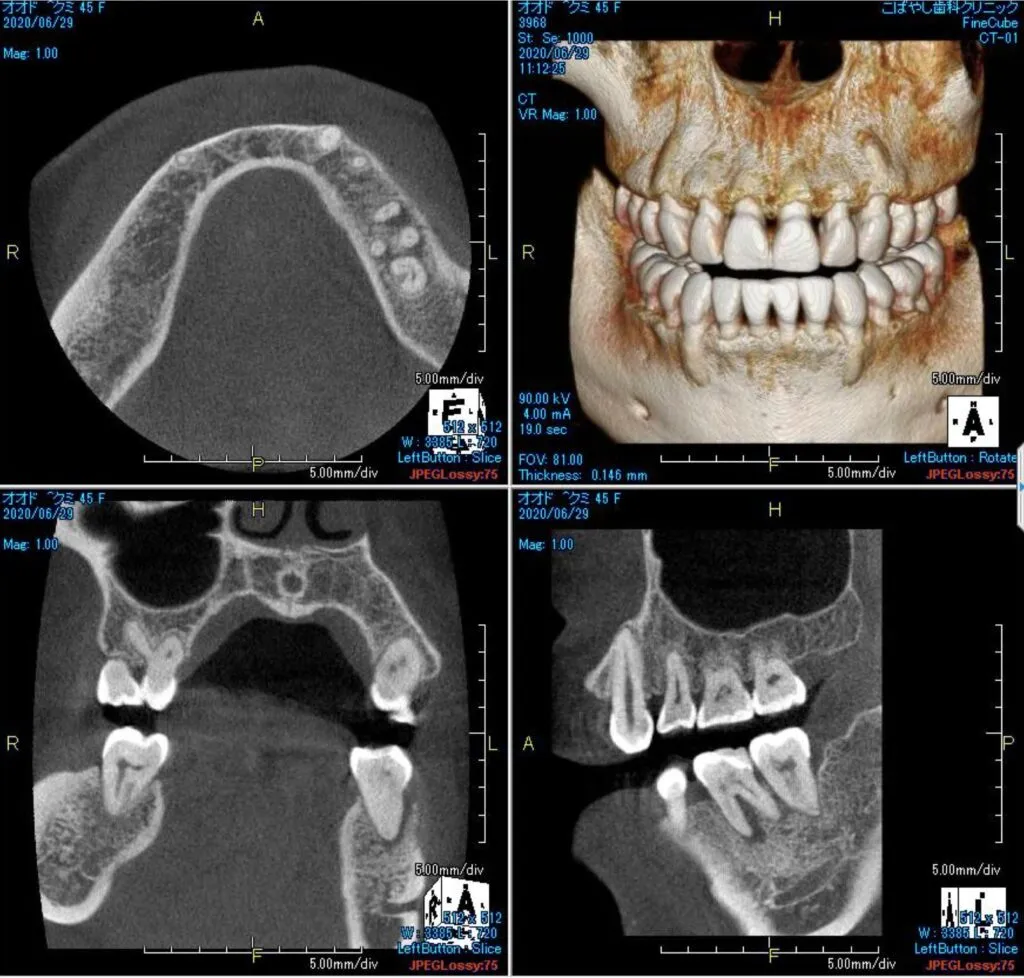

神経にまで進行してしまった重度のむし歯になると、歯を削ってインレー(詰め物)やクラウン(被せ物)を装着する治療だけでは済まなくなり、神経の治療が必要になります。それが根管治療です。 根管治療とは、根管内のむし歯に冒された神経や血管を取り除き、消毒して薬剤を充填する治療。肉眼では見えない部分の治療となるため高度な技術が必要ですが、大阪市北区・大阪市福島区からも近いこばやし歯科クリニックでは歯科用CTとマイクロスコープを用いて精密な根管治療を実現しております。また数多くの治療実績を持っておりますので、安心してご相談ください。

治療前